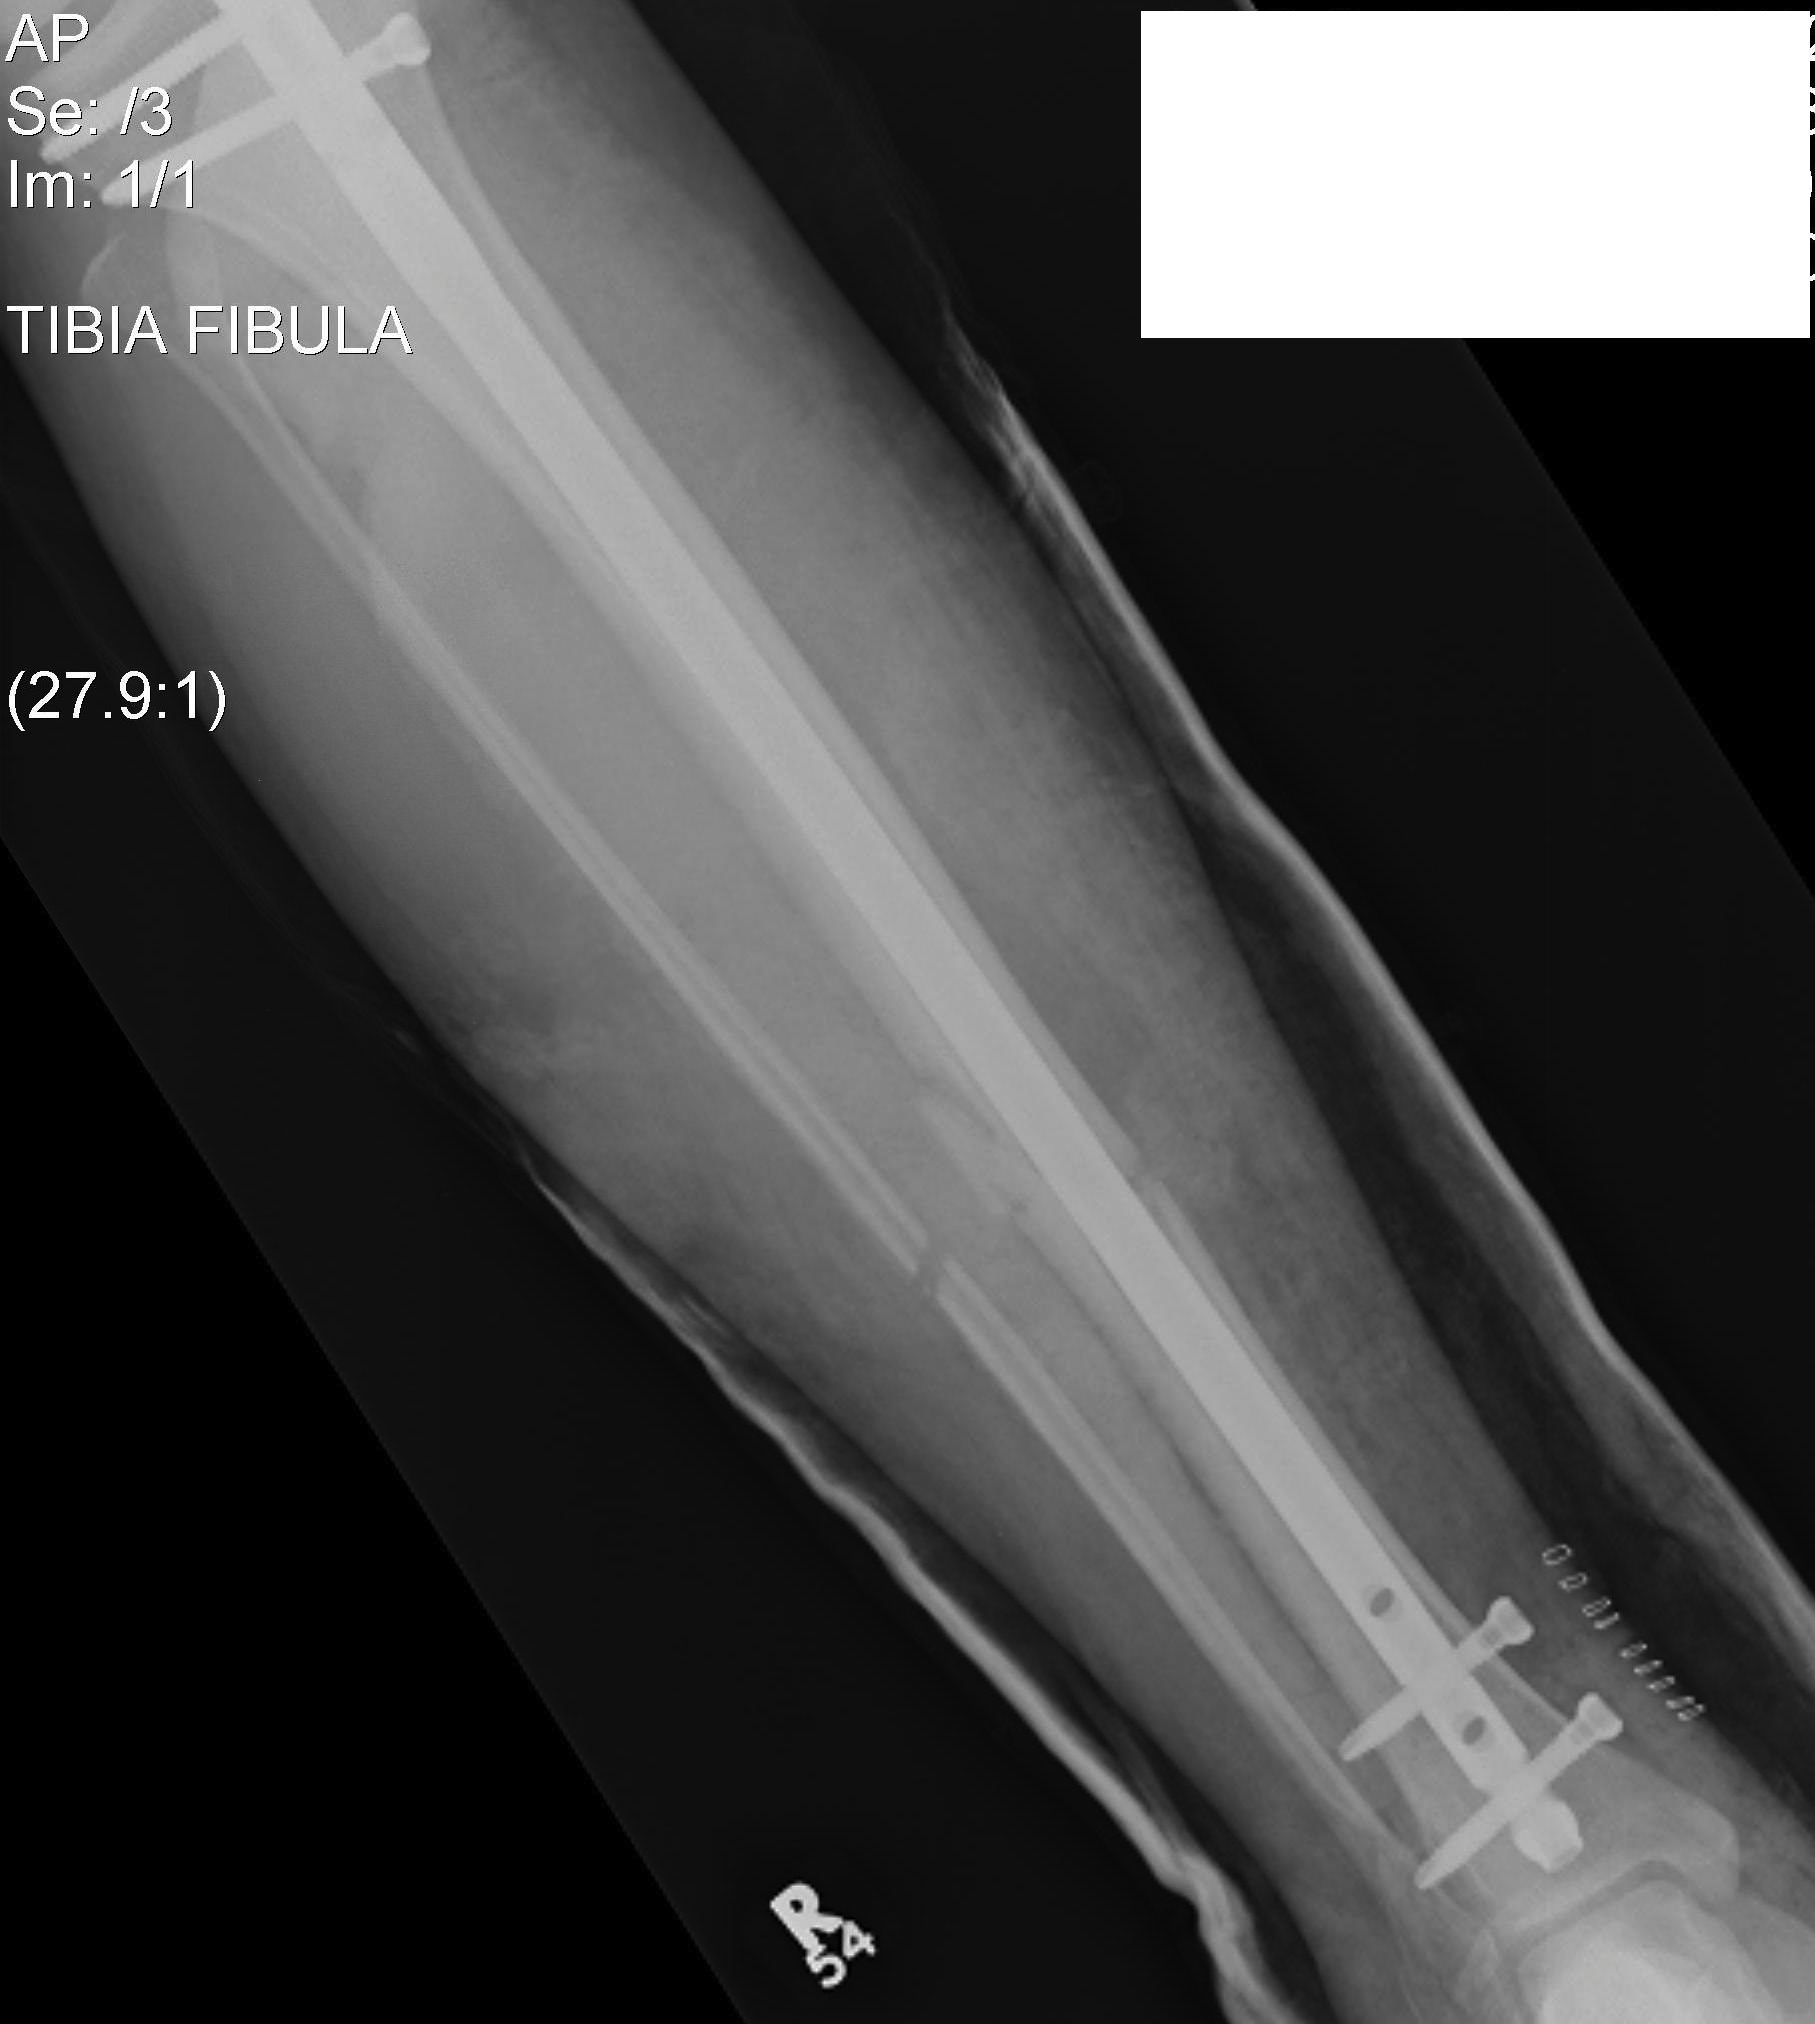

Intramedullary Nails

Indication

- for fixation of the diaphysis of long bones

- reamed vs unreamed

- initial nails relied on interference fit on either side of the fracture and hence could only be successfully applied to midshaft fractures

- interlocked nails have expanded indications to distal and proximal 1/3 shaft fractures